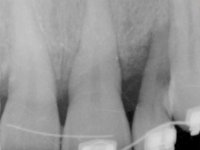

Female patient, 47 years old non-smoker. Tooth 1.3 with endodontic treatment and a cast post and core, rehabilitated with a provisional crown. The two upper lateral incisors are conoid and of small dimension. Tooth 2.2 presents mobility, in agreement with a significant bone reabsorption between teeth 2.1 and 2.3. The two central incisors are separated by a 3 mm diastema and tooth 2.3 presents a crossed occlusion with the opposing tooth. There is also an absence of some posterior teeth and reasonable oral hygiene. In the second intervention performed 8 years later, it was verified that the upper central incisors were chromatically darker and had a longitudinal groove in the enamel which, being pigmented, aesthetically compromised the smile. The work performed in the first phase of the treatment was competent, aesthetically and functionally. Finally, one year after the last intervention, the patient complained of a fracture on the veneer placed on tooth 2.1, probably as a result of being in contact with the abutment of the implant. The rigidity of implant ankylosis may have been the cause of this fracture. I have observed other instances of this type of fracture in identical clinical situations. The veneer of tooth 1.2 was aesthetically compromised and the dental structure itself had small caries and, therefore, its replacement would be recommended.

• Orthodontic treatment to close diastema between maxillary central incisor teeth and slow tooth traction 2.2.

• Placement of an implant at the tooth site 2.2. Rehabilitation of the implant with a coronary and gingival component abutment. in which the screw access hole was "camouflaged" with a feldspathic veneer.